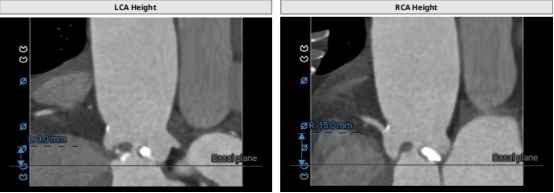

CT結(jié)構(gòu)評估

患者為功能性二葉瓣,瓣葉增厚,輕度鈣化,鈣化主要集中在左竇瓣葉上,左冠脈高度較低,結(jié)合瓣葉長度,竇部結(jié)構(gòu)綜合評估左冠風(fēng)險較低,但左冠瓣葉瓣尖處有鈣化團塊,在球擴以及瓣膜釋放時仍需注意左冠灌注情況,由于鈣化團塊位置特殊,建議做冠脈保護處理,右側(cè)股動脈作為主入路,穿刺點位于股骨頭中段即可。